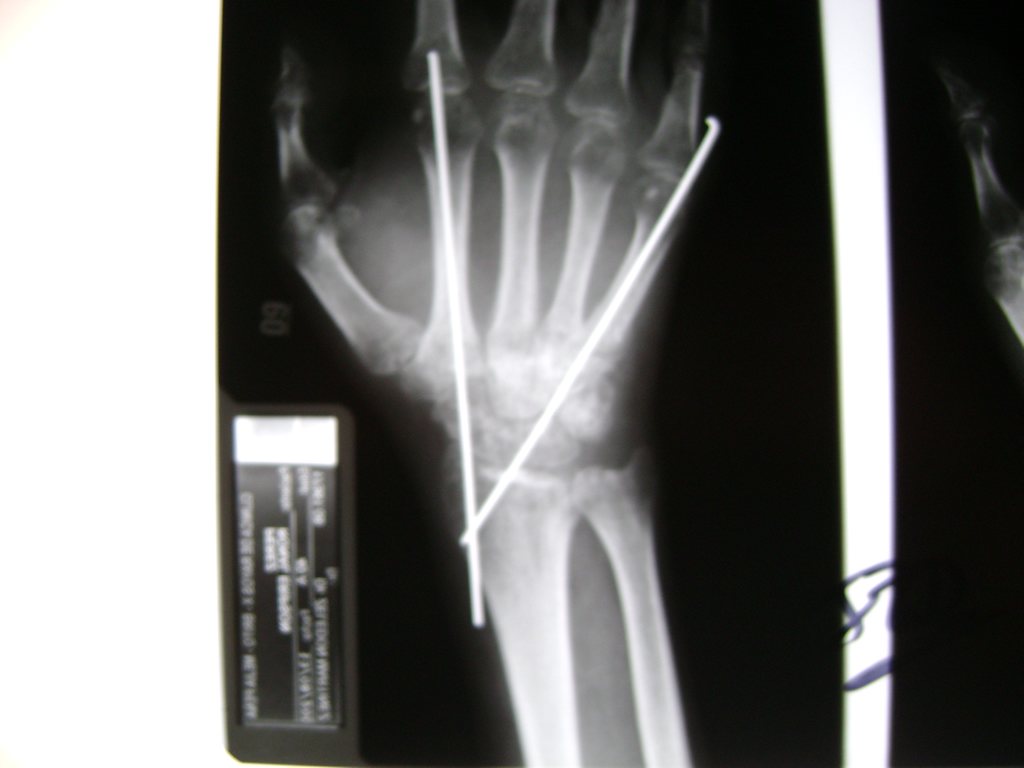

Cirugías de Húmero - Cirugías de Muñecas y Manos

Los procedimientos más comunes en cirugía de la mano son aquellos destinados a reparar traumatismos, incluyendo lesiones de tendones, nervios, vasos sanguíneos, y articulaciones; huesos fracturados; y quemaduras, cortes, y otros daños de la piel.